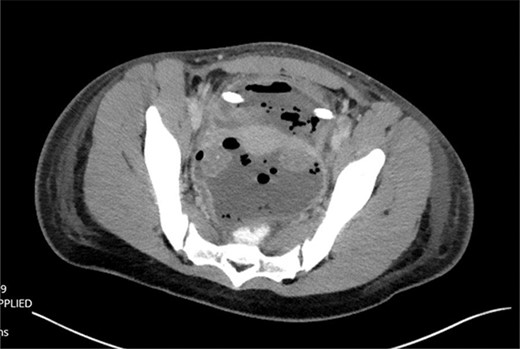

The patient was tolerating a diet, and experiencing anterograde bowel function on postop Day 9; however, the decision was made to obtain a CT of the abdomen pelvis due to an increasing leukocytosis shift. CT revealed two fluid collections with gas pockets, anteriorly measuring 4.0 × 2.8 cm, 9.8 × 6.3 cm in the rectal space (Fig. 3).